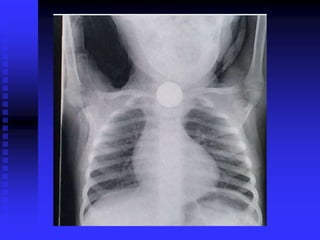

Foreign Body Airway Obstruction

FBAO

FBAO: High Risk Groups

 > 90% of deaths: children < 5 years old

 65% of deaths: infants

KIDS EAT EVERYTHING